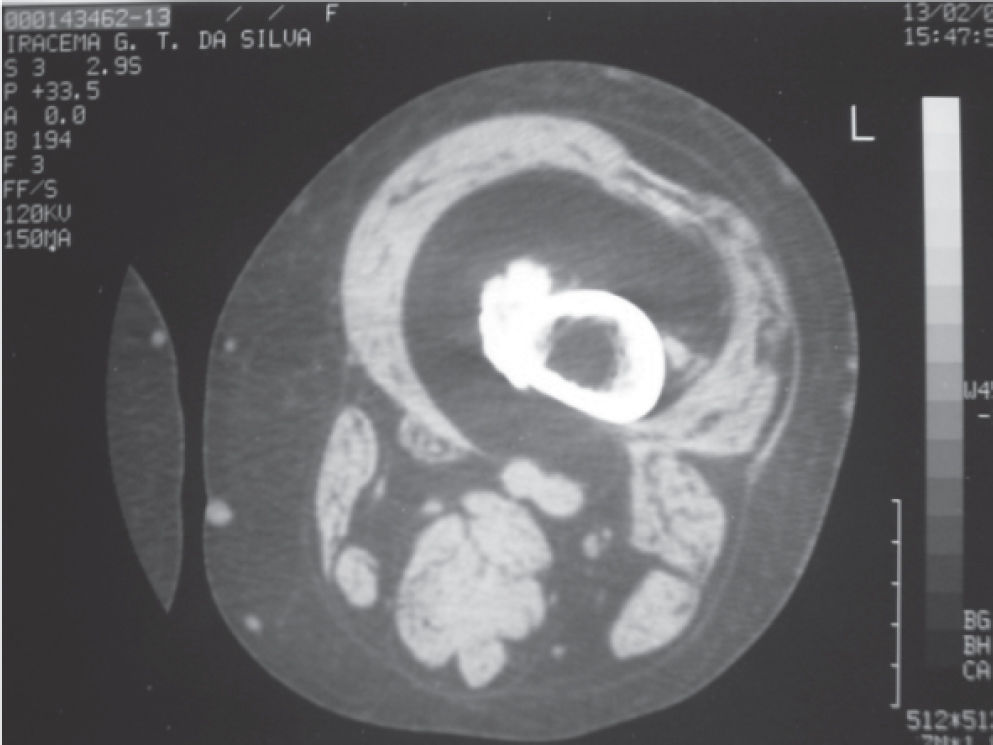

Computed tomography of the left thigh showed a heterogeneous calcification image in the periosteal topography located in the medial region of the distal third of the femur in the metadiaphyseal junction, without rupture of the cortical or bone marrow invasion. In the muscular plane, the density was similar to that of subcutaneous tissue in the intermediate vastus muscle topography, suggesting fat replacement (Figure 2).